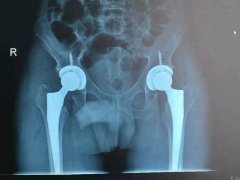

盛兴医院成功开展双侧股骨头无菌性坏死小切口DAA-THA(关节置换朮